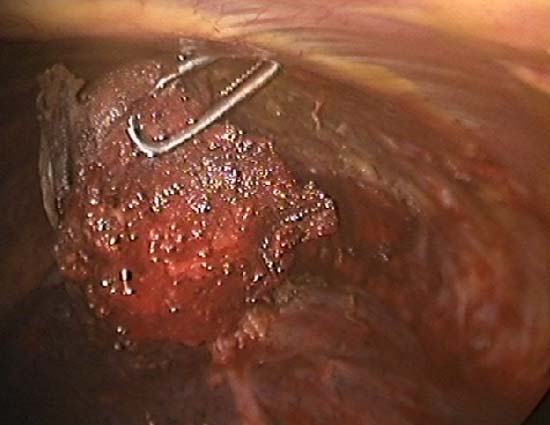

Slightly longer time is needed for resection using the TissueLink device. It is excellent in sealing small (1mm or less) bronchioles in the resection bed. The floating ball device should be applied directly over the bronchiole for one to two minutes to accomplish this. The TissueLink device, by nature of the technology, generates less smoke than conventional electrocautery. However, a small amount of steam is inevitable, and it is advisable to keep a sucker (a conventional Yankauer sucker works best) close to the surgical field, which also may be used to exert counter-traction on the lung tissue to facilitate dissection (Figure 5). As with all potential cancers, specimens should be placed in a bag before they are removed through a port site (Figure 6).